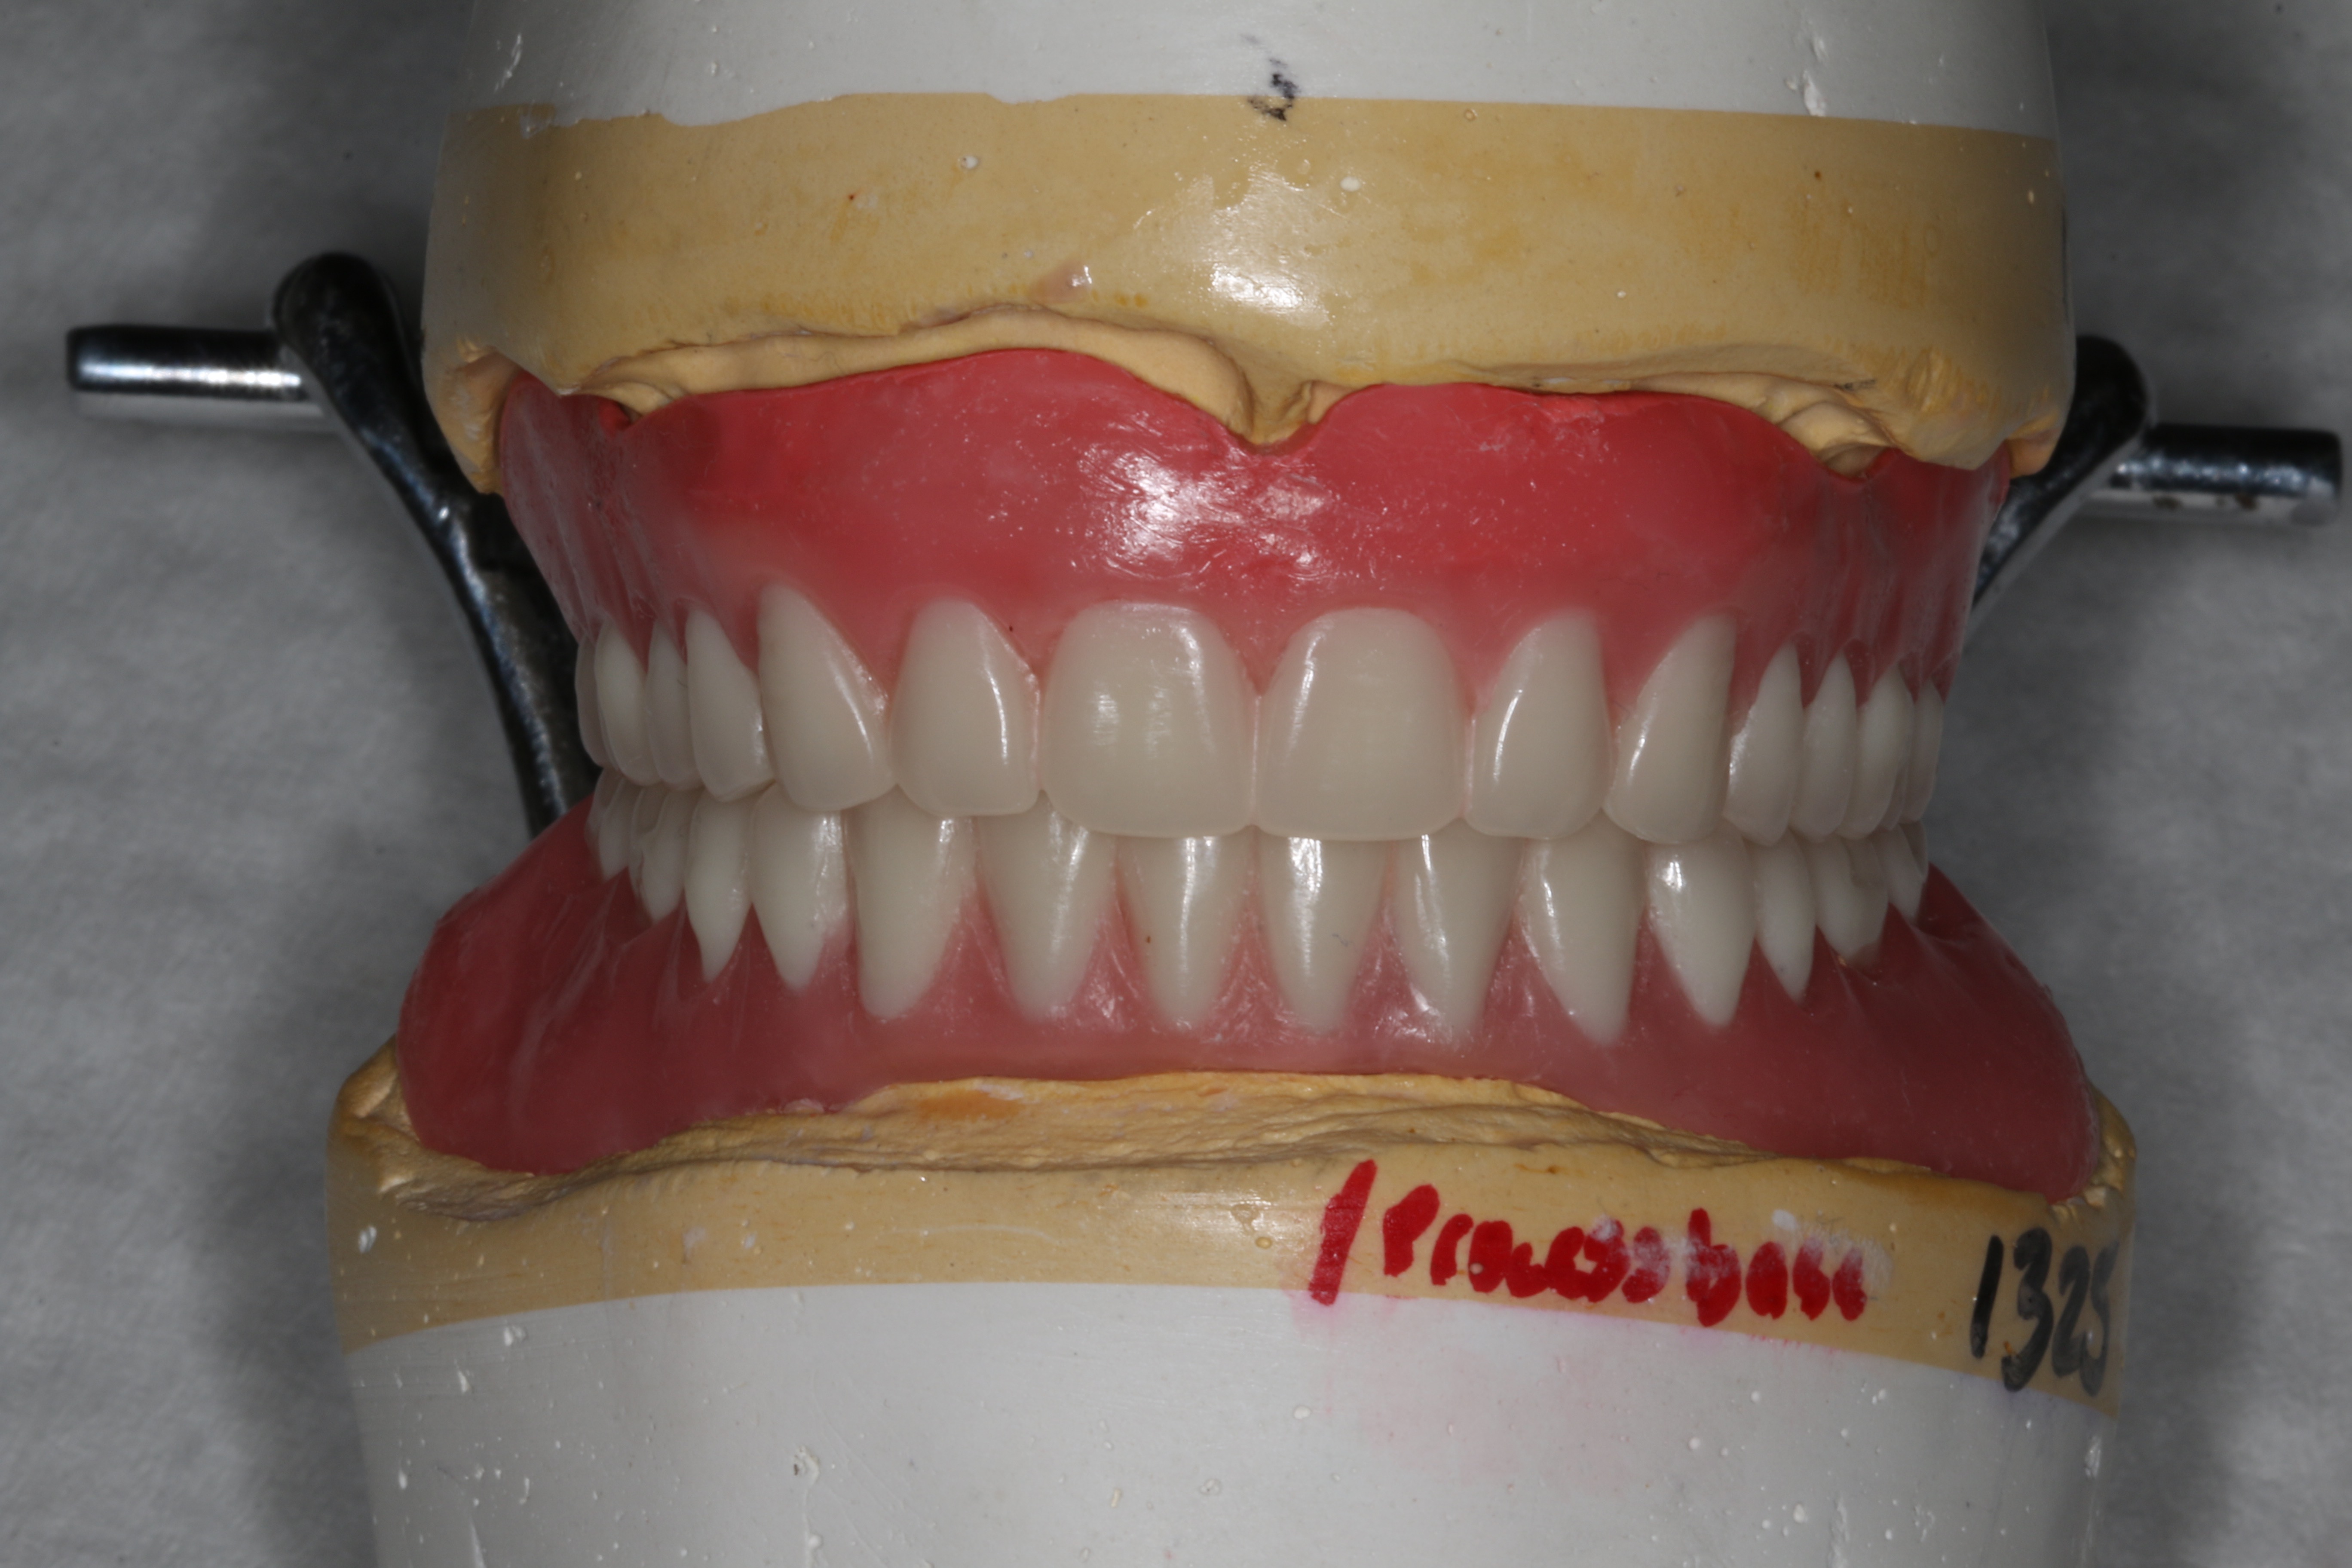

Specific instructions were given to the laboratory to fabricate a cobalt-chromium framework that would add strength and rigidity to the largely acrylic mIRMOD. When fabricating the mIRMOD the laboratory was asked to invest and process the denture base, framework, and female attachment components as a first step. This processed denture base would be used in conjunction with a maxillary denture base, usually made of gutta percha, and wax bite rims to capture jaw relation records. This approach was useful because it allowed for retention of the mIRMOD as records were taken and the subsequent try-in appointments were completed (Figure 12 and Figure 13).

Fig 13. Final set-up approved by the patient.

Figure 13